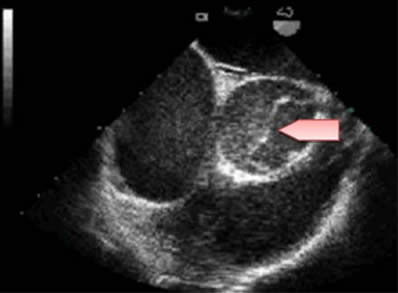

Echocardiogram:TEE dissection Of The Ascending Aorta:type A

Aortic dissection type A: complete desinsertion of the flap involving the posteror aortic cusp, which may also cause a coronary malperfusion. ... View Video